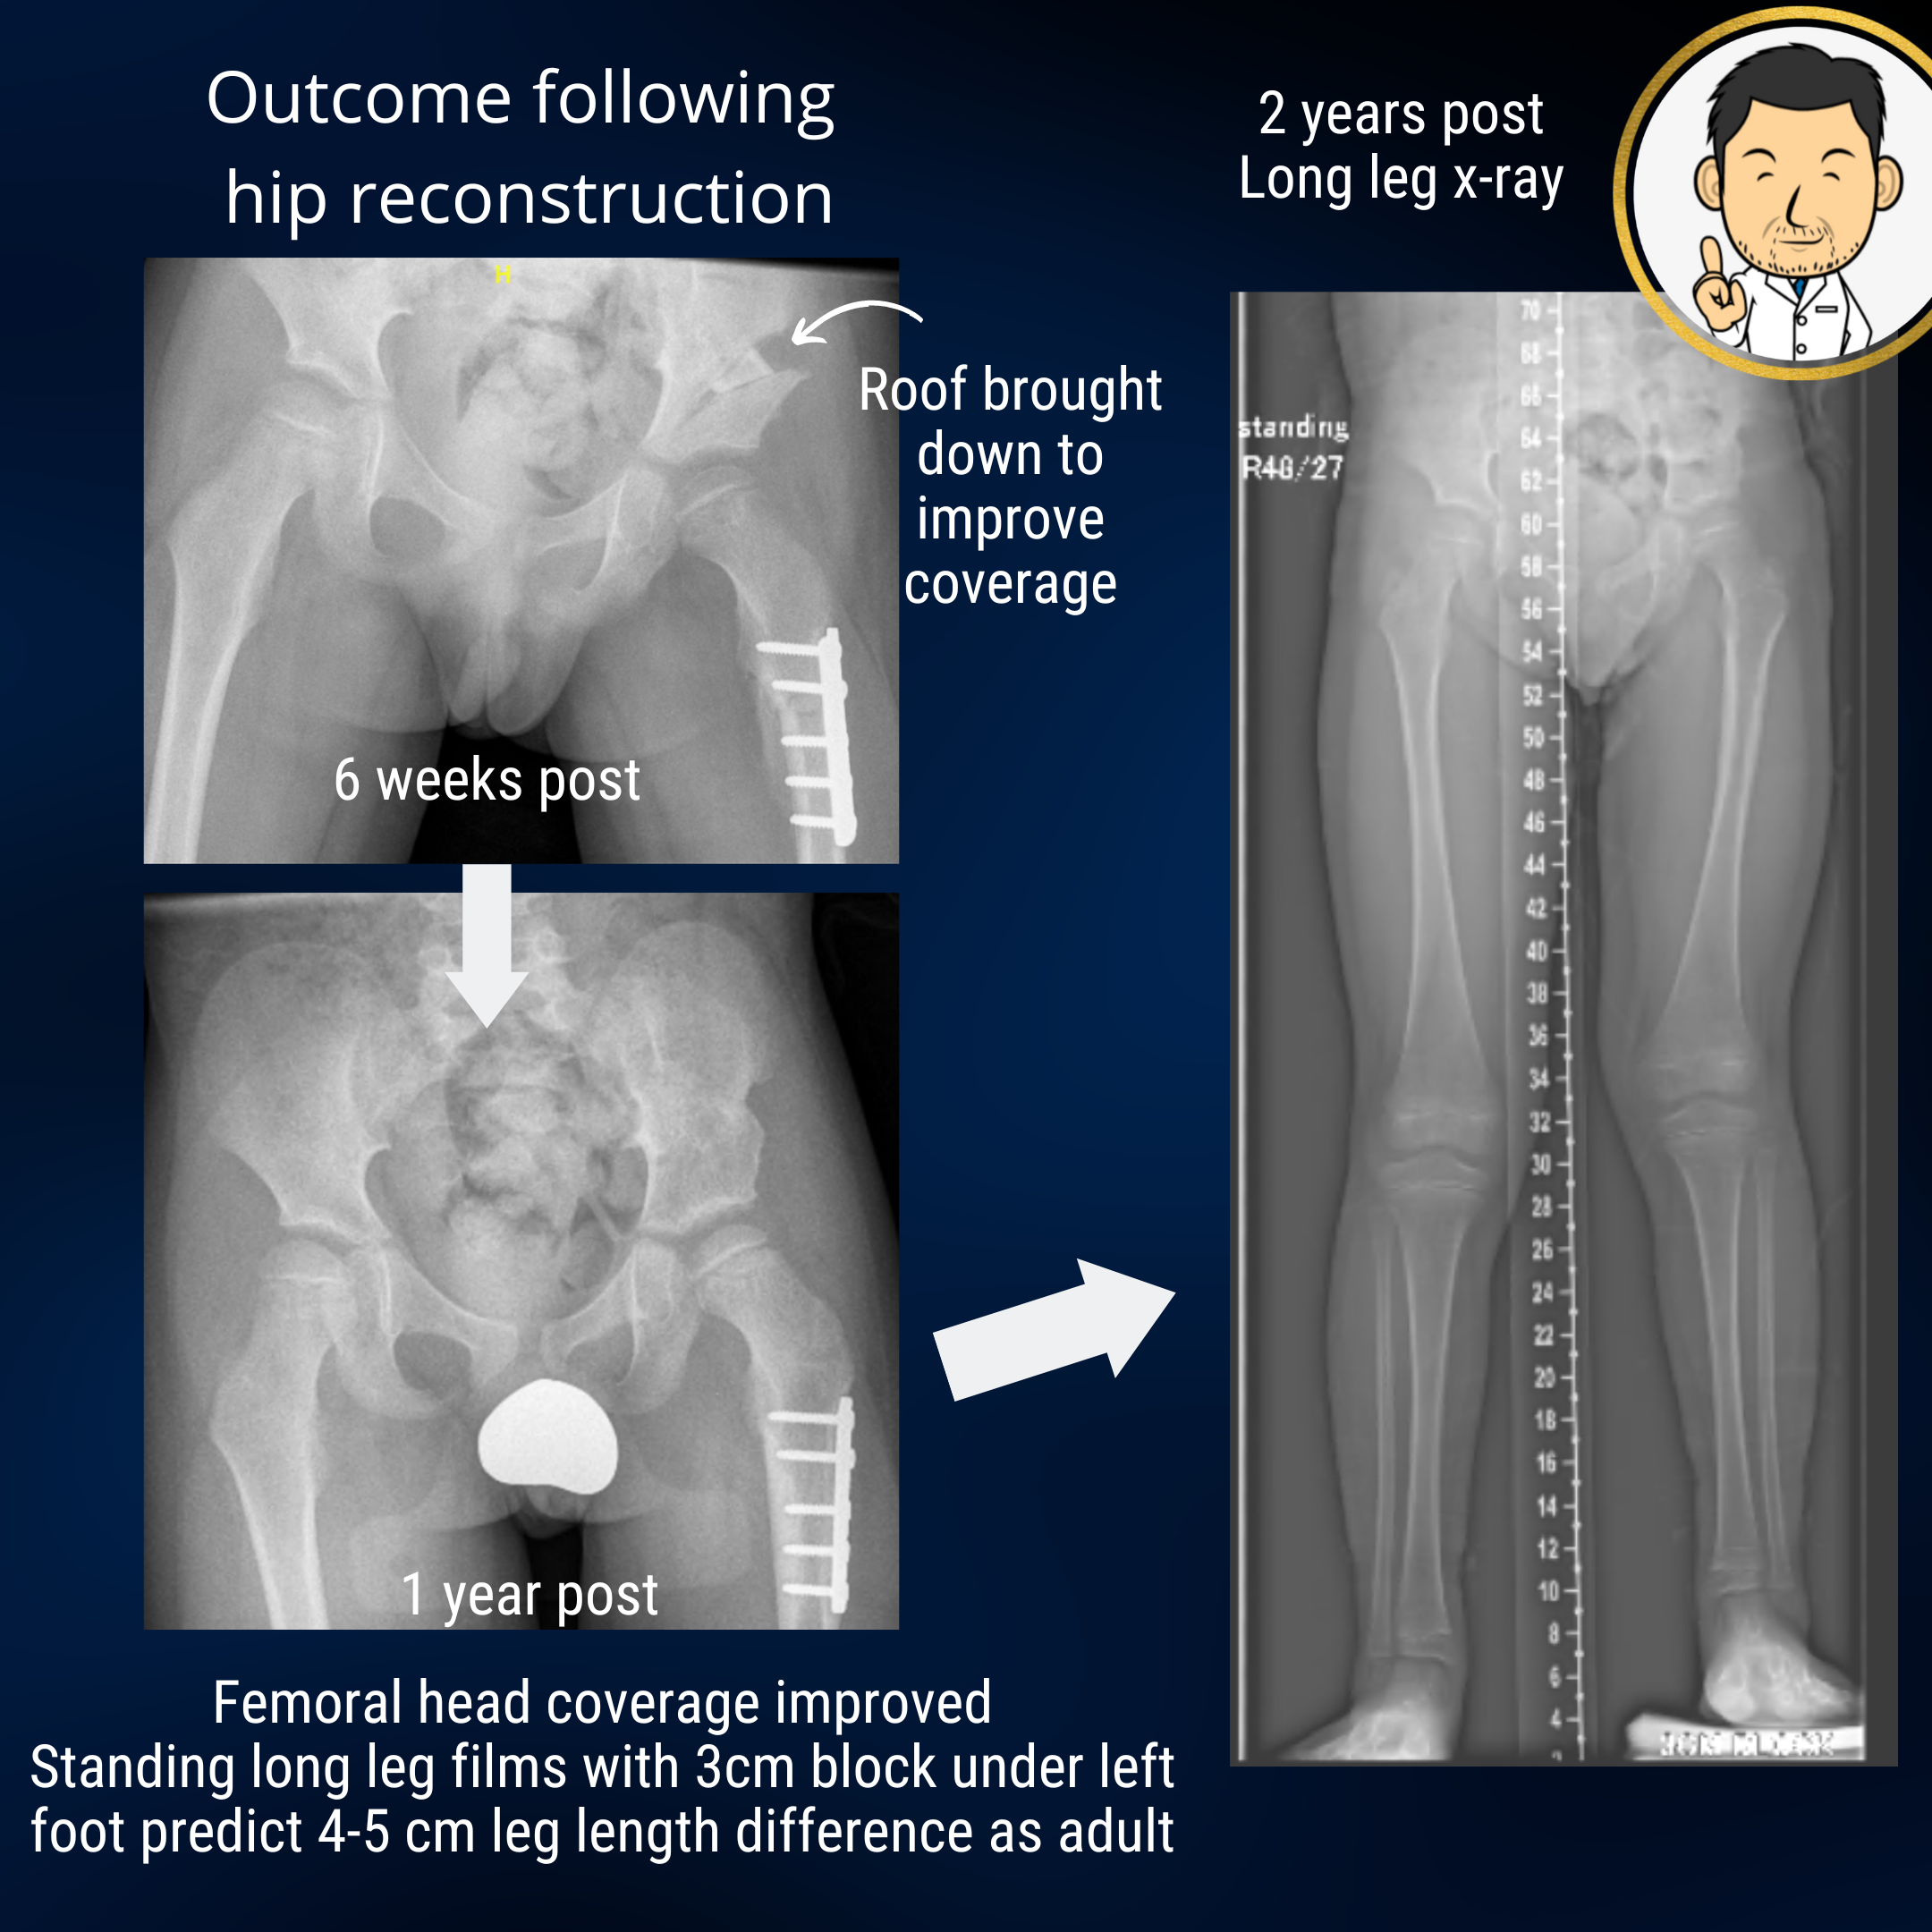

Proximal focal femoral deficiency is a congenital longitudinal deficiency predominantly affecting the femur. The mildest variant is the congenital short femur where mild femoral shortening may be accompanied by mal-alignment of the hip joint. The top end of the femur may have a "crooked hunched over" appearance and the socket may be shallow. Although, shortening in itself produces an asymmetric gait, the abnormal hip anatomy often leads to an "out-toeing" walking pattern with early fatigue due to muscle inefficiency. The socket may be shallow. If left unaddressed, this may lead to the hip dislocating if the femur is lengthened when the child is older. Correcting the alignment of the hip joint and improving socket coverage are goals that should be addressed early. The "surgical footprint" (a euphemism of the magnitude of surgery and it's impact on the patient) is much less when the hip is reconstructed early in life compared with when the child is in their teens. Early hip reconstruction improves the outcomes and risk profile of later limb lengthening surgery.